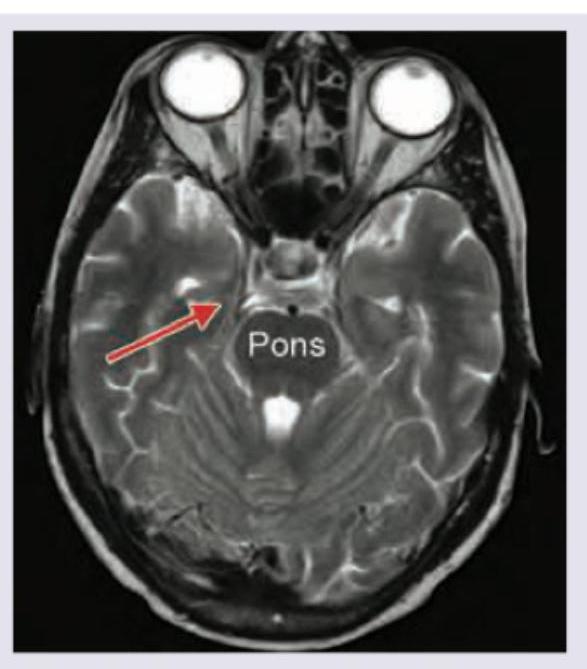

Which structure is marked with a red arrow in the image shown below? (AIIMS May 2018)

Explanation: ***Mammillary bodies*** - The image shows an **axial view** of the brain, and the red arrow points to a rounded structure anterior to the pons, consistent with the location of the **mammillary bodies**. - These are part of the **limbic system** and play a crucial role in memory formation through their connections with the hippocampus and thalamus. *Hippocampus* - The hippocampus is located in the **medial temporal lobe**, deeper and more posterior than the structure indicated by the arrow on this axial slice. - It has a characteristic elongated, curved shape, quite distinct from the **paired, rounded structures** shown. *Habenular nuclei* - The **habenular nuclei** are located in the **epithalamus**, superior to the midbrain and posterior to the thalamus, not in the anterior brainstem region indicated. - They are much smaller and are involved in modulating various brain circuits, including those related to pain, stress, and reward. *Amygdala* - The amygdala is an **almond-shaped structure** located deep within the temporal lobe, anterior to the hippocampus. - While close to the region shown, its shape and exact position differ from the **mammillary bodies**, particularly in this axial plane where the mammillary bodies are seen as distinct, round structures near the midline.